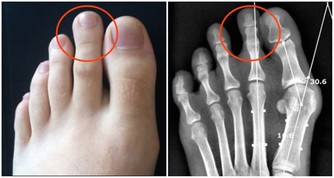

4、多發性骨髓瘤

多發性骨髓瘤這種疾病多發於老年人,並且年齡越大發病率越高,是成正比的,這種疾病最初的表現症狀也是腰痛,但是除了腰痛之外,這個疾病還會侵犯身體其他的骨頭,也就會導致身體其他部位的疼痛,多發性骨髓瘤會侵犯人的運動系統,最嚴重的後果是導致骨折,老年人的骨折往往都是致命的,因為老年人骨折後的臥床會帶來很多的並發症。

多發性骨髓瘤這種疾病多侵犯人的骨頭、骨髓,所以常常腰痛伴有周身疼痛,並且多發性骨髓瘤這種疾病也是一種惡性腫瘤,如果家裡的老人長時間的腰痛就要帶著去醫院檢查一下,排查一下多發性骨髓瘤。